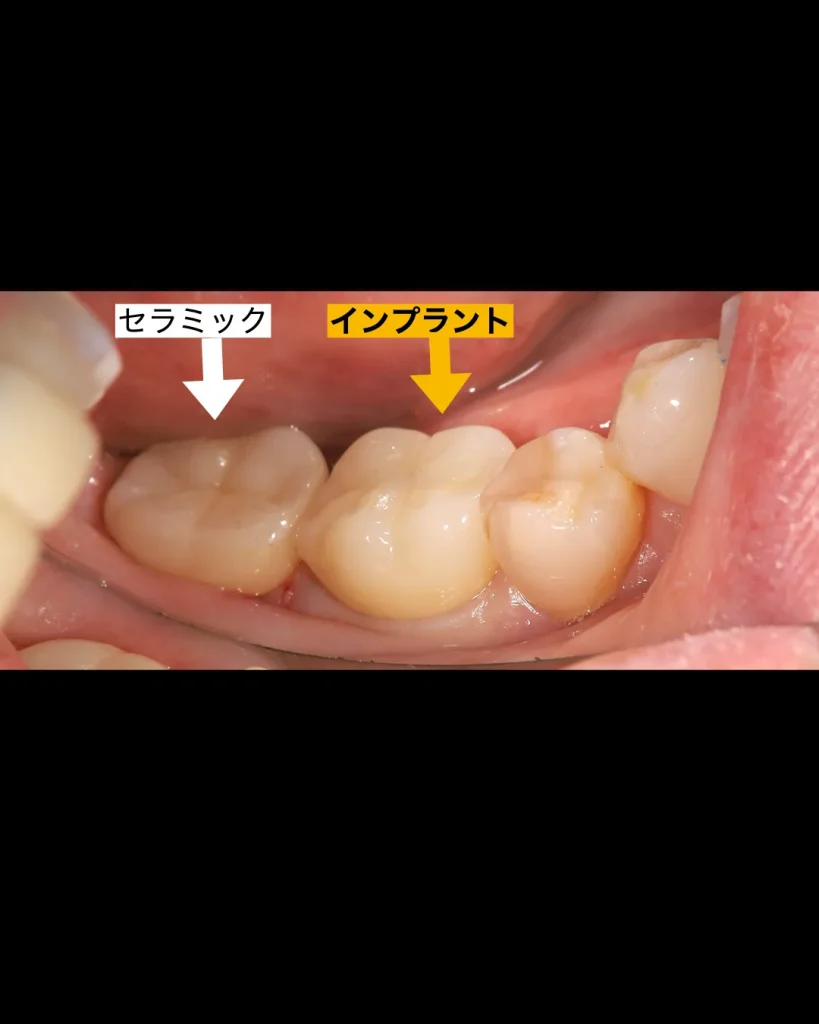

後ろの歯も状態は悪く、何度もインレーが脱離していたので、今回のインプラントをする際に一緒に治療することになりました。一番後ろの歯は残せるのでセラミッククラウンで被せることにしました。

治癒は良好で、3ヶ月ほどで仮歯の型取りを口腔内スキャナーで行い、噛めるようにしました。舌や頬を噛まない、問題なくしっかりと噛めることを確認した後、最終的なセラミックの上部構造をセットしました。

抜歯から3ヶ月で治療は終了しました。患者様は手術も1回で済み、痛みもほとんどなく大変喜ばれていました。今はメインテナンスに半年に1度、定期的に来院されており問題なくお食事を楽しまれています。何よりも喜ばれたのは手術が一回で済んだのと痛くなかったことだったそうです。

| 治療内容 | 奥歯1本のインプラントと天然歯のセラミック治療 |